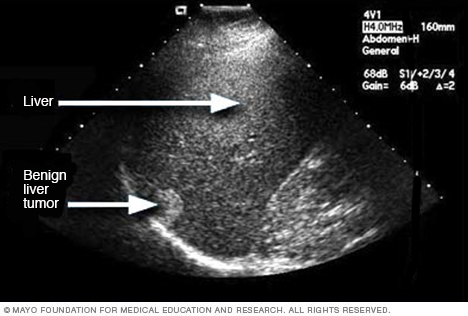

- Imaging tests. An ultrasound, CT scan and MRI can show liver damage.